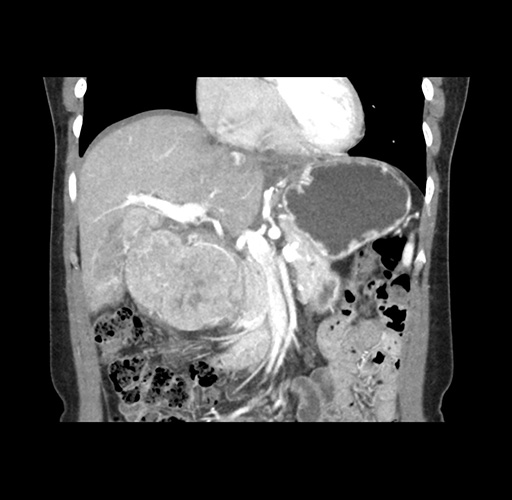

Imaging Analysis

Look through the patient's CT scan to identify any areas of concern for the necessary procedure.

Based on your CT findings, which issue(s) would give reason for "planned slowing down moment(s)" in this case?

Considering a standard left lateral sectionectomy procedure, what step(s) of the operation would you do differently in this case ?